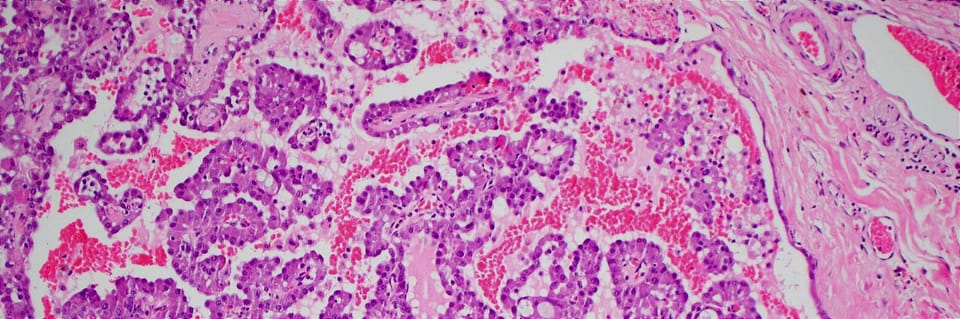

Forpath Seminar - Salivary Gland Tumor Pathology: An Overview